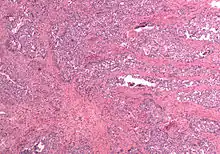

In gross appearance, MMMTs are fleshier than adenocarcinomas, may be bulky and polypoid, and sometimes protrude through the cervical os. On histology, the tumors consist of adenocarcinoma (endometrioid, serous or clear cell) mixed with the malignant mesenchymal (sarcoma) elements; alternatively, the tumor may contain two distinct and separate epithelial and mesenchymal components. Sarcomatous components may also mimic extrauterine tissues (e.g., striated muscle, cartilage, adipose tissue, and bone). Metastases usually contain only epithelial components.